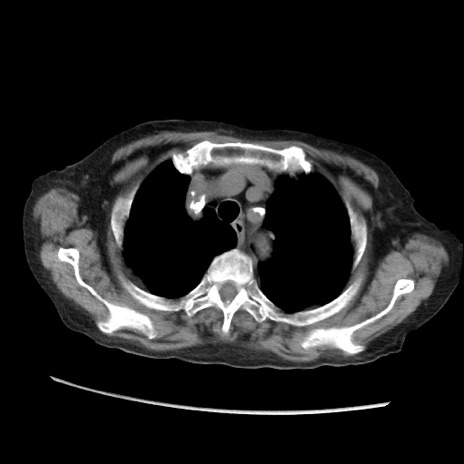

症例31(横断像)

【症例】80歳代 女性

【主訴】腹部膨満感

【現病歴】他院にて肝硬変にてフォロー中。1週間前から便秘、腹部膨満感、臍部腫瘤あり受診となる。

【既往歴】肝硬変

【身体所見】腹部膨隆あり、皮膚変化なし、疼痛なし。

【データ】WBC 4600、CRP 0.25